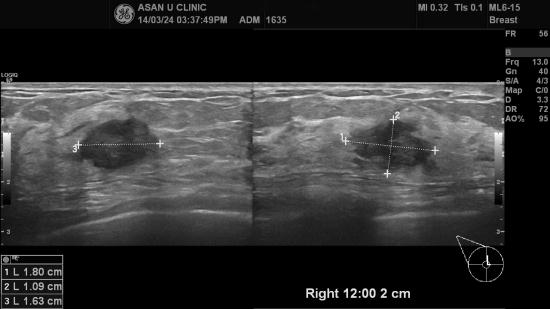

아산유외과 개원 후 81번째 유방암진단.

44세 여성분으로 우측 유방에 갑작스레 몽우리가 만져져 내원하셨습니다.

유방촬영상 우측유방에 결절과 우측 액와부에 림프절 비대보였으나

유방초음파유도하여 시행한 중심핵생검상 유방에만 침윤성 유방암이 있고

액와부에 전이없는 소견보였습니다.

유방의 결절도 2cm미만이라

그래도 좋은 예후를 보일듯해 마음이 좋습니다.